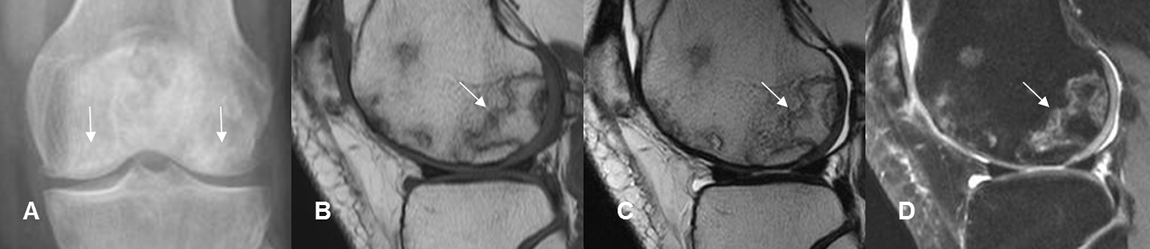

Fig 24 A. Osteonecrosis.

A: Rx AP. Zonas densas de etiología inespecífica, en ambos cóndilos femorales.

B: RM sagital en T1, C: RM sagital en T2 y D: RM sagital en STIR. Lesión geográfica en la parte posterior del cóndilo femoral lateral, hipointensa en T1 y T2 e hiperintensa en STIR, por osteonecrosis de evolución subaguda. Adicionalmente hay lesiones osteocondrales en la patela y la parte anterior del cóndilo.